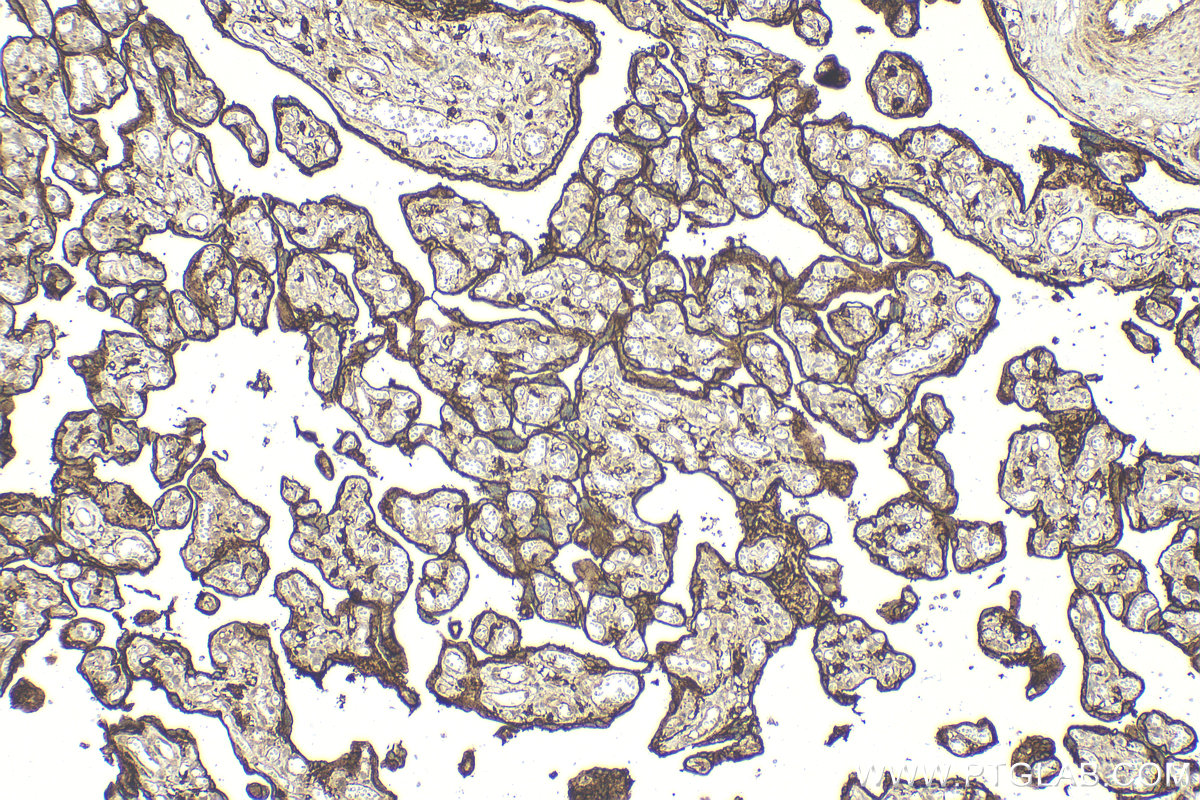

| Positive IHC detected in | human placenta tissue Note: suggested antigen retrieval with TE buffer pH 9.0; (*) Alternatively, antigen retrieval may be performed with citrate buffer pH 6.0 |

| Immunohistochemistry (IHC) | IHC : 1:200-1:800 |